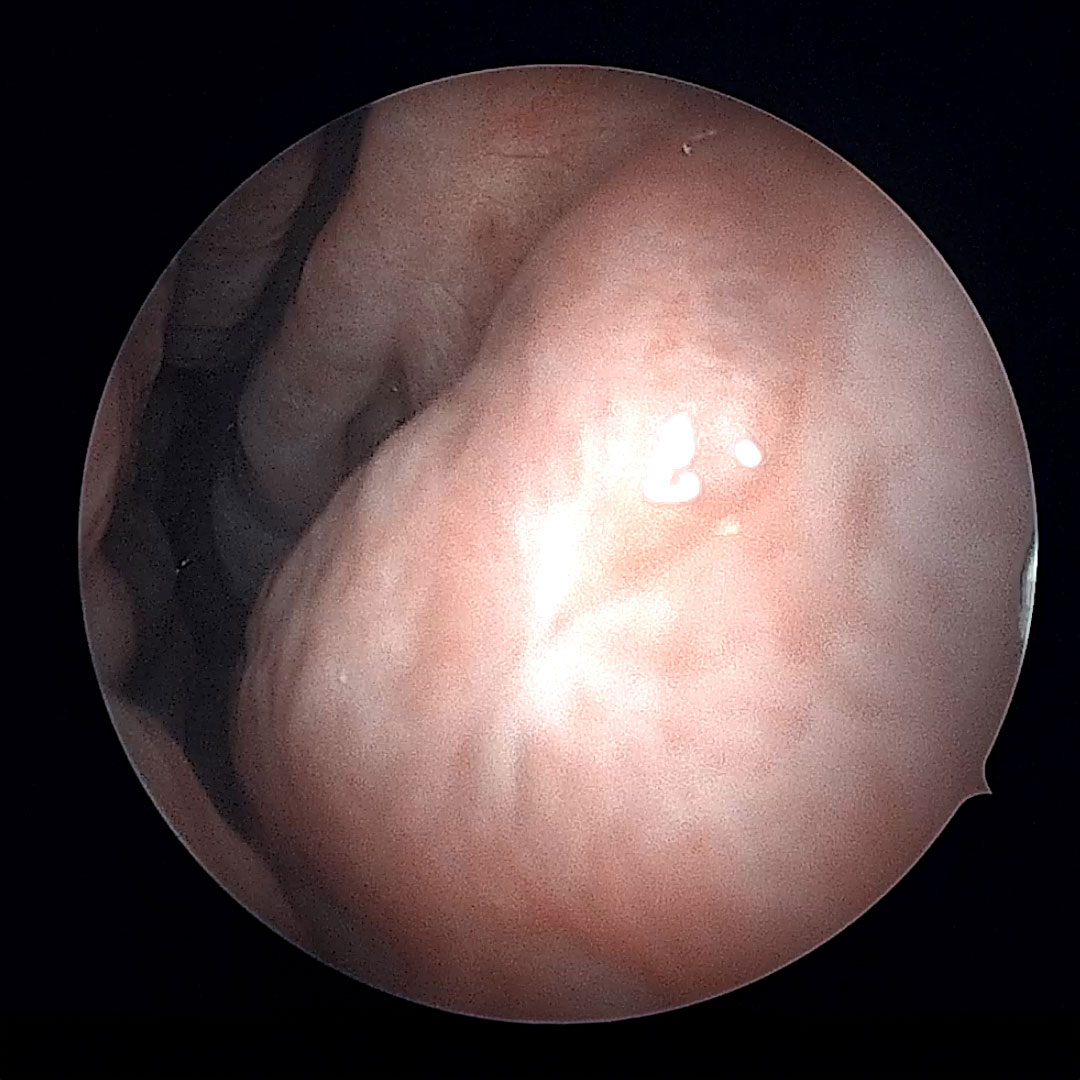

after treatment image Before

before treatment image After